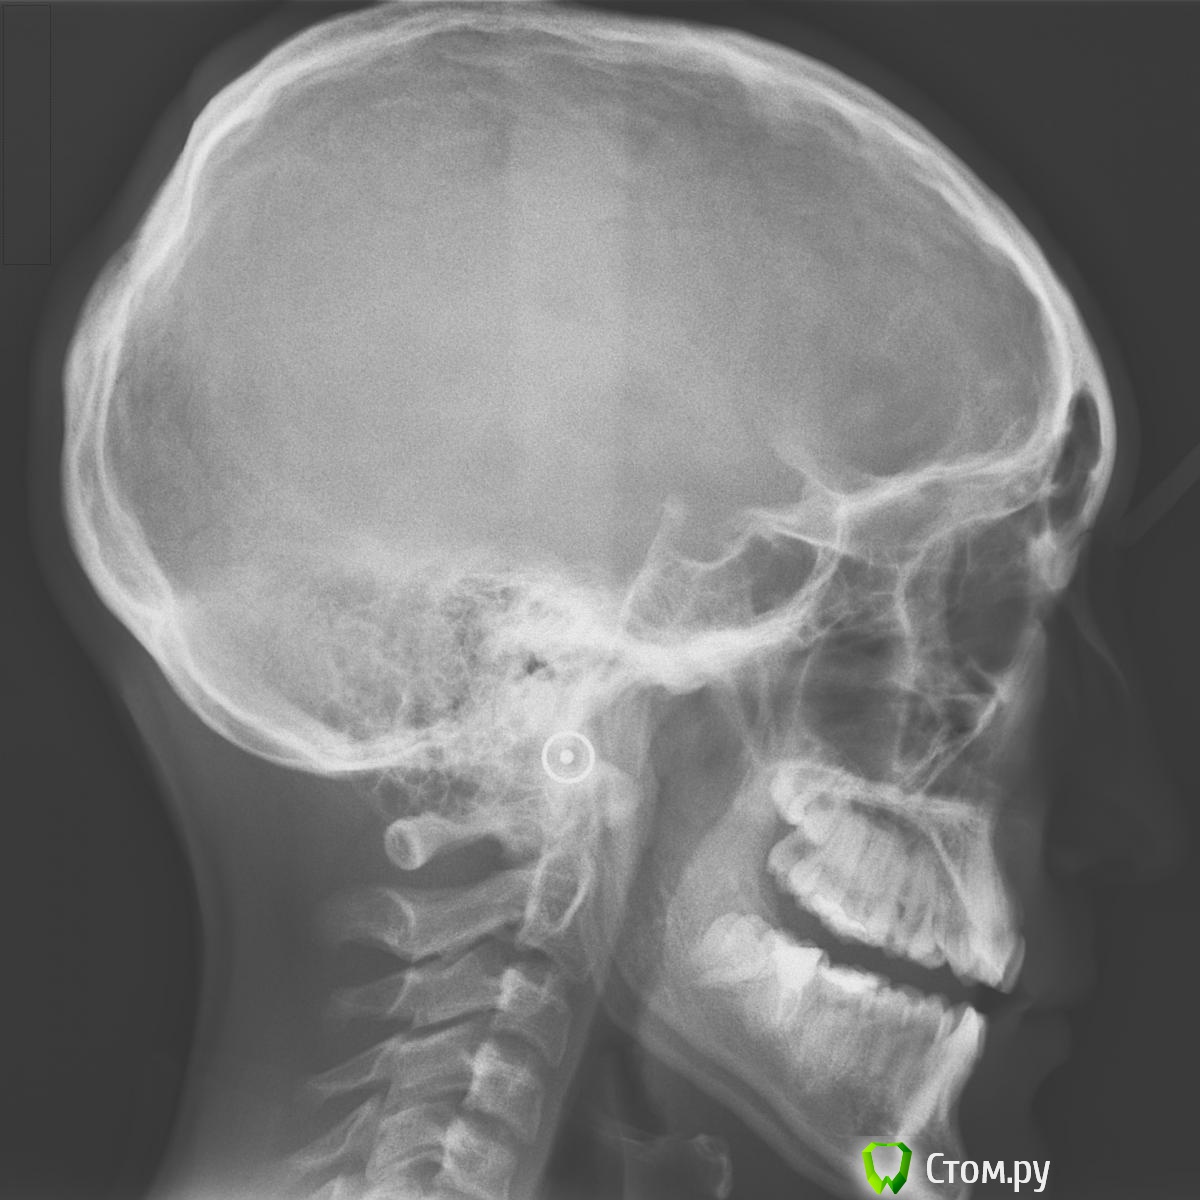

m.d.n Опубликовано 30 мая, 2014 Поделиться Опубликовано 30 мая, 2014 да,для меня пока сложновато, поэтому прошу у вас помощи и совета.Здесь фотографии до лечения,сейчас ситуация как на фото в первом посте. Нужно плоскость выровнять окклюзионную.а а почему трг с разомкнутыми челюстями?.тут 3 класс закомуфлированный Ссылка на комментарий

Jamex Опубликовано 31 мая, 2014 Автор Поделиться Опубликовано 31 мая, 2014 а почему трг с разомкнутыми челюстями?.тут 3 класс закомуфлированныйВы можете помочь мне с лечением данного пациента? Ссылка на комментарий

m.d.n Опубликовано 31 мая, 2014 Поделиться Опубликовано 31 мая, 2014 Вы можете помочь мне с лечением данного пациента?так почему трг с разомкнутыми челюстями? Ссылка на комментарий